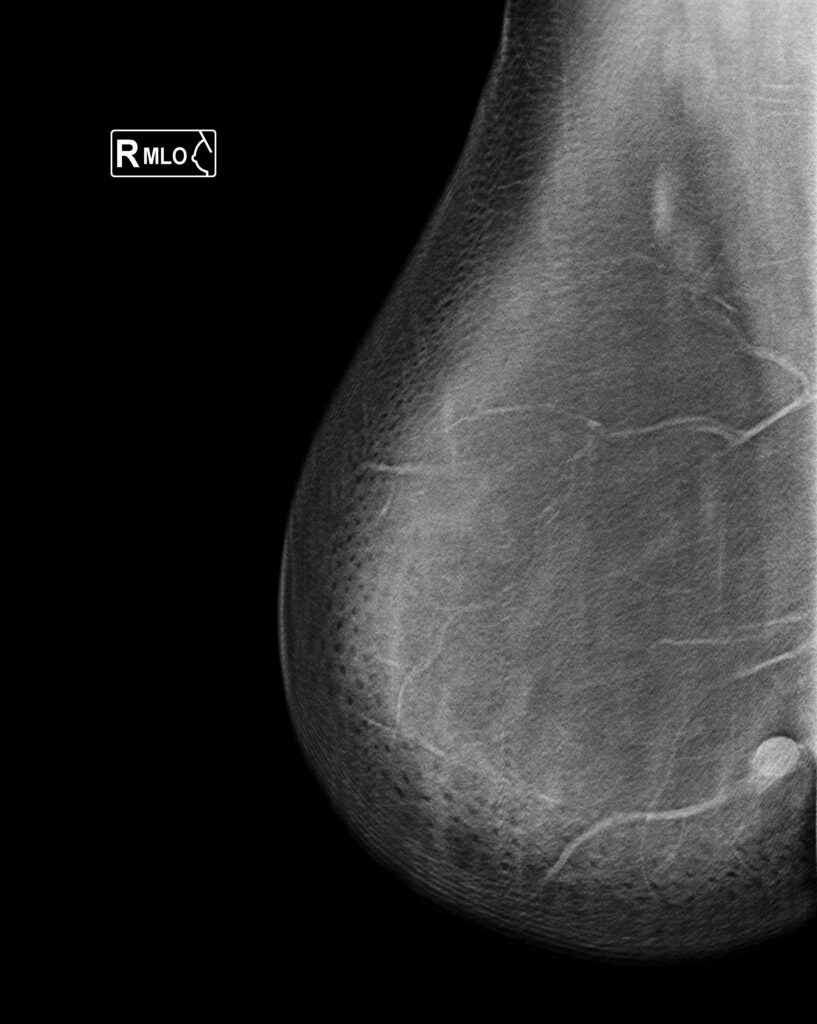

- Tipos de estudio mamografico

| Indicación Principal | Subcategoría de Indicación | Historia Relevante para Informar (si se conoce) |

|---|---|---|

| Tamizaje Asintomático | – Riesgo elevado – Mamas densas – Cáncer de mama previo (tratamiento completado) – Otros | Mutación genética Riesgo de cáncer estimado Historia de cáncer previo |

| Evaluación Diagnóstica | – Hallazgos clínicos – Hallazgos por imagen – Seguimiento categoría 3 – Seguimiento tras biopsia – Evaluación de implantes – Otros | Tipo de hallazgo clínico Tipo de hallazgo por imagen |

| Diagnóstico: Cáncer de Mama Actual | – Extensión de la enfermedad antes del tratamiento – Respuesta durante o después de terapia neoadyuvante – Otros | Localización y tamaño del cáncer en evaluación previa |